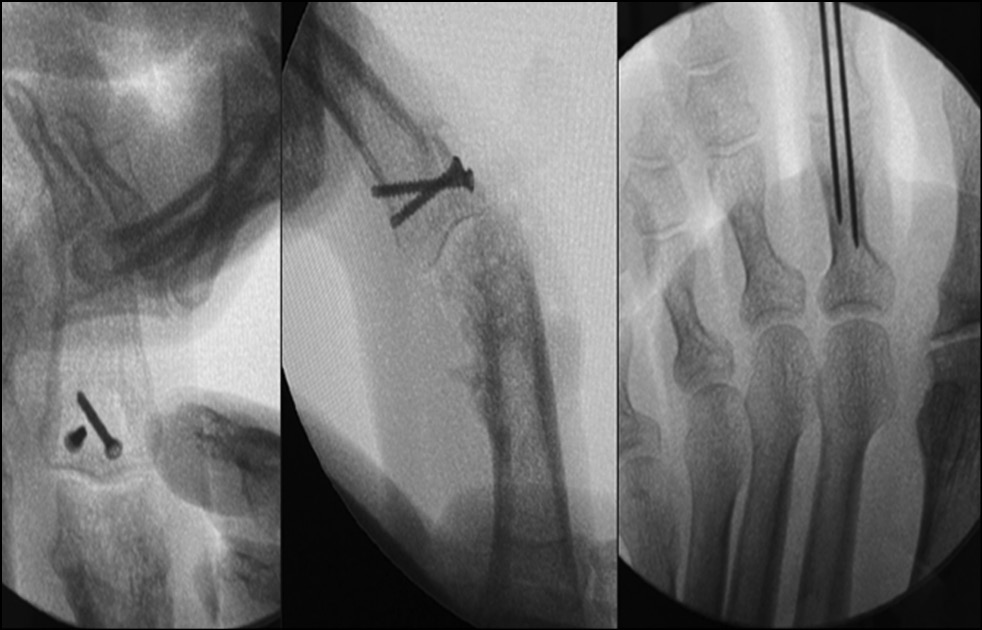

During 2021−2022, 26 patients (23 men and 3 women) with fracture dislocation of the middle phalanx base of triphalangeal fingers of hand in the acute period of trauma sought care. The average age was 31 years (16–46 years). The mechanism of injury was axial direction of force (impact) with rear deviation. All patients underwent preoperative diagnosis: radiography and clinical assessment of the amplitude of motion in the joint. Avulsive (detached) fractures of the palmar edge of the middle phalanx base with its dorsal subluxation were determined by radiologic signs. According to the Eaton classification, the patients were categorized as group IIIa. In all cases, the amplitude of movements in PIP joints was sharply limited by pain syndrome. Pain syndrome at the moment of attempted flexion in the joint was from 6 to 8 points on VAS. It was decided to treat all these patients with fixation of the injured finger in the Suzuki distraction-reposition external fixation apparatus (Figs. 24−29). This apparatus was described by Y. Suzuki in 1994 and represents t system of intraoperatively modeled three Kirschner spokes connected by rubber ties [8].

Fig. 26. X-ray control after surgery. Suzuki pins and rubber traction system.

Fig. 27. Appearance after surgery. Suzuki pins and rubber traction system.

Intraoperatively, a 1.2 mm Kirschner spoke was inserted through the head of the proximal phalanx along the axis of rotation in the PIP joint (axial), with the ends of the spoke bent at 90°. A similar spoke is passed through the head of the middle phalanx along the axis of rotation in the distal interphalangeal joint; the ends of the spoke are also bent at 90°. Opposite bends (loops) are created at the ends of the curved shoulders of the spokes, ensuring a distance of 2.5 cm between them. Next, the third (repositioning) spoke is passed through the base of the middle phalanx as proximal as possible to the fracture zone; it is displaced to the rear relative to the phalanx axis and should pass under the shoulders of the axial spoke. Elastic rings, each 1 mm thick and cut from the rubber injection unit of an intravenous infusion system, are stretched over the bends of the first two predissected spokes. The degree of tension (distraction) of the spoke system (indicated by the number of elastic rings) is determined intraoperatively radiologically, based on size of the interarticular gap. Repositioning component of the system is accomplished by passing the middle phalanx base spoke displaced to the rear under the axial spoke. The last guided spoke is bent around the axial spoke to prevent displacement from under it but not to limit sliding between them.

Fixation in this system was carried out for 4 weeks. On day 1, the patient is trained to develop movements in the PIP joint passively. On day 2, the patient begins to perform active movements in the joint, and a radiologic control study is conducted to determine the degree of distraction and the need for its correction. It is acceptable to increase the joint gap to 4−5 mm, but the most desirable is 2−3 mm. During the outpatient phase of treatment, the patient is recommended to develop passive/active movements three to five times a day.